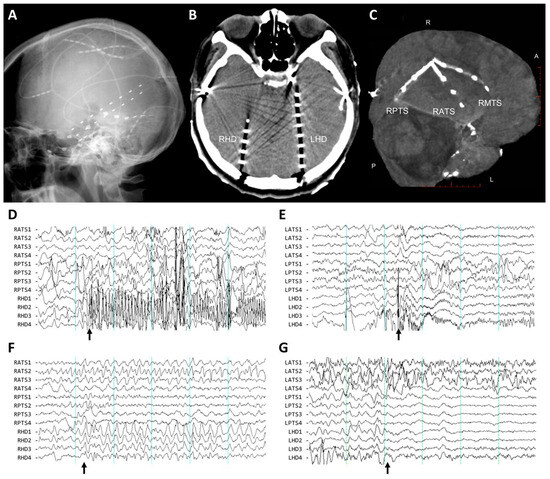

2.2.2. Surgical Procedures for Invasive Studies

2.2.3. Clinical Assessment of Intracranial EEG Recording

2.3. Characterization of the Ictal Onset Patterns of Depth and Subdural Electrodes

3.2. Electrographic Patterns at Ictal Onset

3.3. Distribution of Involved Electrodes and False Lateralization